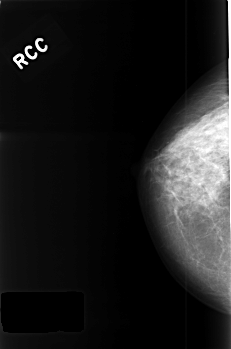

C_0426_1.RIGHT_CC

RIGHT_CC LINES 4528 PIXELS_PER_LINE 3000 BITS_PER_PIXEL 12 RESOLUTION 50 NON_OVERLAY